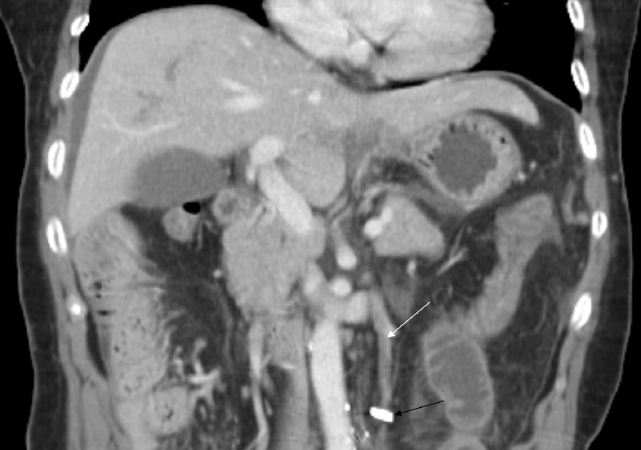

Figure 1: Coronal contrast-enhanced CT scan shows a thrombus formation (white arrow) in the inferior mesenteric vein and adjacent small bowel distension, without extension to the portal vein. Surgical clips (black arrow) placed in the mesentery are shown.

figure 1